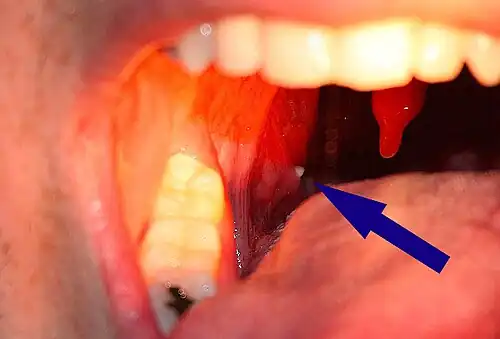

A tonsillolith lodged in the tonsillar crypt

Tonsil stones, also known as tonsilloliths, are mineralizations of debris within the crevices of the tonsils.[1][3] When not mineralized, the presence of debris is known as chronic caseous tonsillitis (CCT).[1] Symptoms may include bad breath,[1] foreign body sensation, sore throat, pain or discomfort with swallowing, and cough.[4] Generally there is no pain, though there may be the feeling of something present.[1] The presence of tonsil stones may be otherwise undetectable; however, some people have reported seeing white material in the rear of their throat.

Tonsilloliths or tonsil stones are calcifications that form in the crypts of the palatal tonsils. They are also known to form in the throat and on the roof of the mouth. Tonsils are filled with crevices where bacteria and other materials, including dead cells and mucus, can become trapped. When this occurs, the debris can become concentrated in white formations that occur in the pockets.[12] Researchers found aerobic bacteria present on the surface of tonsilloliths and anaerobic bacteria at the core of tonsilloliths. They have the potential to cause oral halitosis as they contain volatile sulfur compounds and sulfur derived gases, foul smelling compounds produced during bacterial metabolism.[16] Tonsilloliths are formed when this trapped debris accumulates and are expressed from the tonsil. They are generally soft, sometimes rubbery. This tends to occur most often in people who suffer from chronic inflammation in their tonsils or repeated bouts of tonsillitis.[12] They are often associated with post-nasal drip.